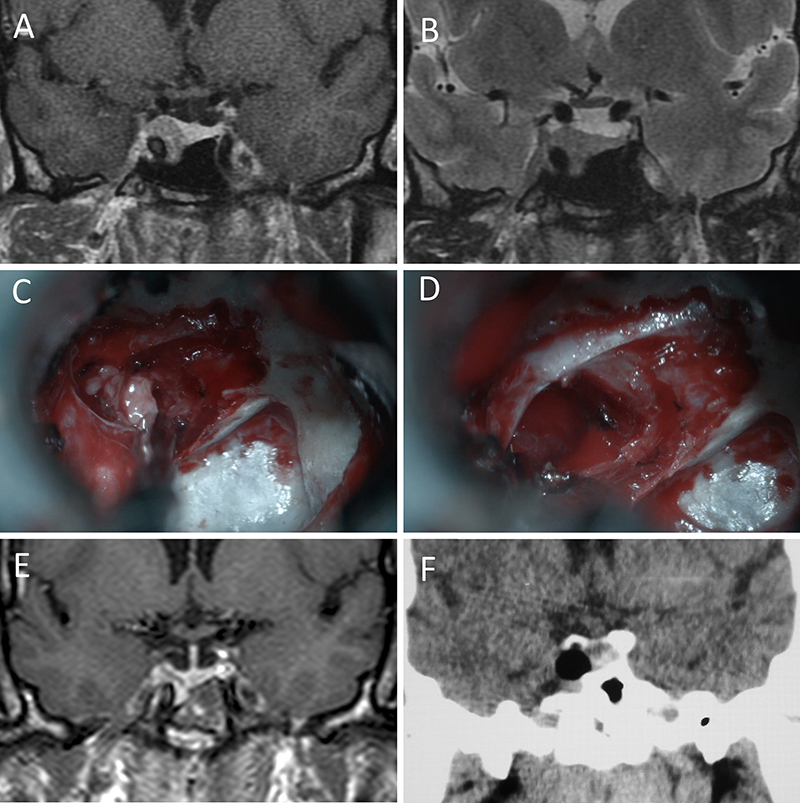

Figura 1: Macroadenoma no funcionante en mujer de 65 año s. Se decidió la cirugía tras evidenciarse crecimiento en los controles. Evolucionó favorablemente desde el punto de vista clínico-radiológico. A-B: RM preoperatoria; C-D: intraoperatorio; E-F: RM postoperatoria.

Figura 2: Macroadenoma no funcionante en mujer de 31 años. La paciente presentó en el preoperatorio déficit visual que mejoró tras la cirugía. A-B: RM preoperatoria; C-D: intraoperatorio; E-F: RM postoperatoria.